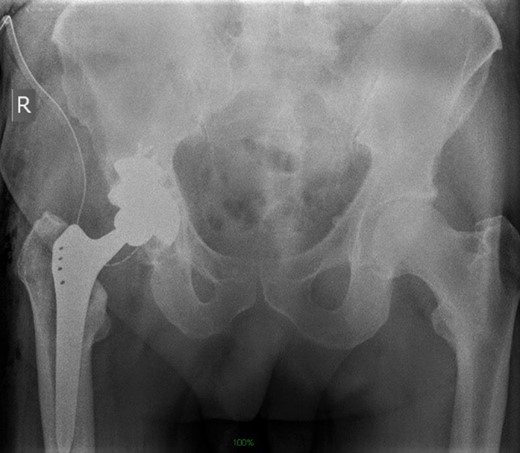

Life-size 3D model was printed from a converted file containing the computed tomography (CT) scan of one patient with severe acetabular defects waiting for total hip revision surgery. The 66-year-old male had a background of coxarthrosis. He underwent total hip arthroplasty of his right hip in February 2017. The preoperative CT scan and X-Ray of the pelvis showed large right-sided pelvic defect and severe acetabular defect (Figs 1 and 2). The patient had history of cardio-vascular comorbidity and underwent 2 week specific antihypertensive therapy preoperatively.

Preoperative radiograph demonstrating large acetabular defect with screw penetration.